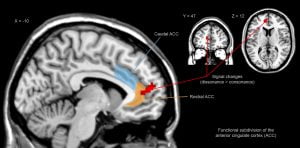

مطالعهای که بهصورت آنلاین توسط PLOS Biology منتشرشده است، به بررسی آنچه در طول اثر دارونما بر مغز میگذرد پرداخته است. محققان از تصویربرداری رزونانس مغناطیسی عملکردی یا FMRI برای اسکن مغز افراد مبتلابه درد مزمن ناشی از آرتروز زانو استفاده کردند. سپس به همه آنها دارونما داده شد و اسکن مغزی دیگری گرفته شد. افرادی که تسکین درد را احساس میکردند، فعالیت بیشتری در ناحیه شکنج میانی لوب پیشانی مغز داشتند که حدود یکسوم پیشانی را تشکیل میدهد.